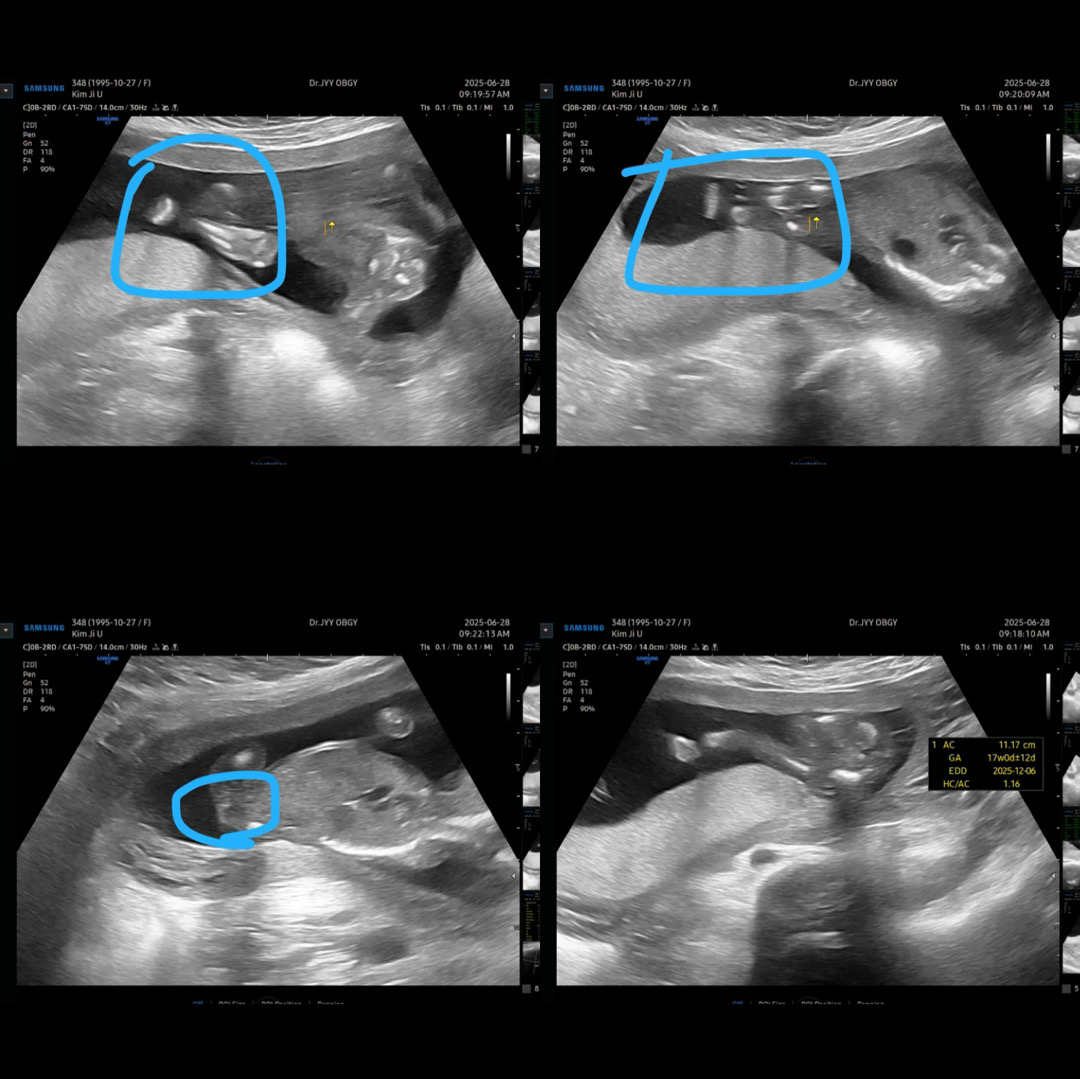

16주차때 성별 못보신분 있나용 ㅠㅠㅠ

아가가 다리를 모으고 있고 붙히고 있어서 자세히는 못봤는데 저같은 분 많으신가요? ㅋㅋㅋ 살짝 보일때는 뭐가 안보이는것 같기도 하고ㅜㅜ 다음주에 다시 보기로 했는데 또 안보일까봐 궁금하네요 ㅋㅋㅋ ㅠㅠㅠ

저어제 병원갓는데 못보고왓어요 ㅠㅠ태반에 얼굴 묻히구 자구잇더라구요 ㅠㅠ 다리도 모으고잇고 ㅠㅠ